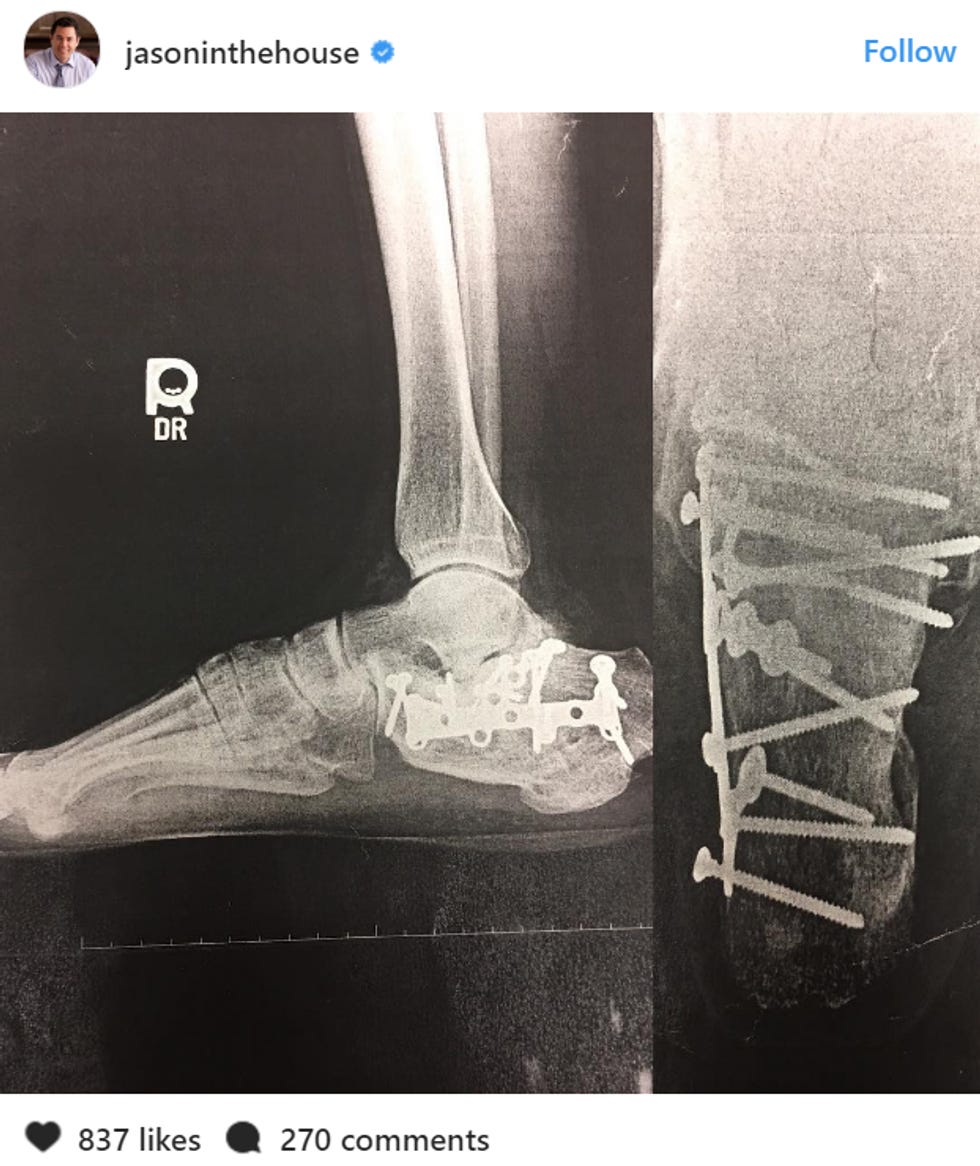

If you cannot read that, the gist is that 12 years ago, Jason Chaffetz was trying to fix his garage door or something and he fell andthat's why his face looks like thathe broke his foot in a million places. Now his doctors say they need to take all the nails out of his foot RIGHT NOW, otherwise he will get a big infection. He appreciates his "constituent's patience" (apparently just the one), and he promises he will come back to work at Congress ASAP, when his foot is beautiful and new again.